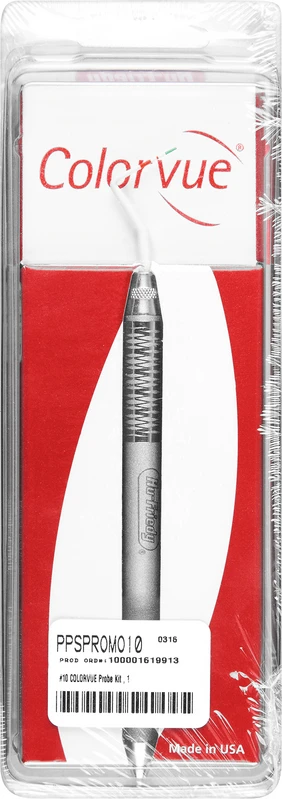

Die Colorvue Sonde PerioScreen fra Hu-Friedy muliggjør rask og enkel bestemmelse av periodontale lommedybder før endelig undersøkelse. En lett forståelig fargekoding med fargene grønn og rød viser om periodontitt er til stede eller ikke.

| Weight | 0,048 kg |

|---|---|

| Variant | <b>Introduksjonssett</b> spiss (markering 3-5-7-10), 1 håndtak |